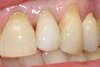

Réhabilitation latérale et 1ère prémolaire supérieures gauche (cassées) remplacement par des implants dentaires + Blanchiment

Cas terminé avec les couronnes sur implant